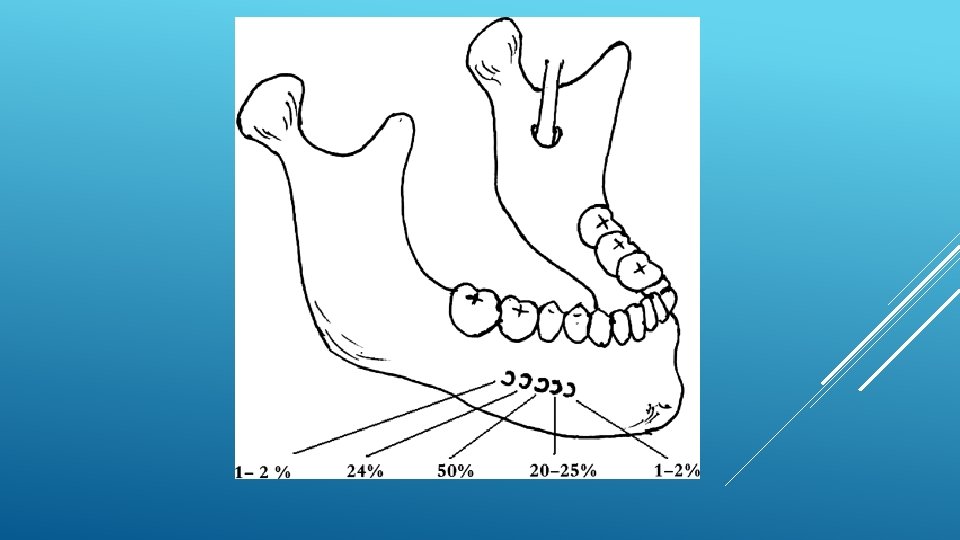

LOCATION AND DIMENSIONS OF THE MENTAL FORAMEN: A RADIOGRAPHIC ANALYSIS BY USING CONE-BEAM COMPUTED TOMOGRAPHY The majority of MF (56%) were located apically between the 2 premolars, and another 35. 7% of MF were positioned below the second premolar. On average, the MF was localized 5. 0 mm from the closest root of the adjacent tooth (range, 0. 3 -9. 8 mm). The mean size of the MF showed a height of 3. 0 mm and a length of 3. 2 mm; however, individual cases showed large differences in height (1. 8 -5. 1 mm) and in length (1. 8 -5. 5 mm). All mental canals exiting the MF demonstrated an upward course in the coronal plane, with 70. 1% of the mental canal presenting an anterior loop (AL) in the axial view. The mean extension of AL in cases with an AL was 2. 3 mm.

RELATIONSHIP BETWEEN THE POSITION OF THE MENTAL FORAMEN AND THE ANTERIOR LOOP OF THE INFERIOR ALVEOLAR NERVE AS DETERMINED BY CONE BEAM COMPUTED TOMOGRAPHY COMBINED WITH MIMICS The parameters were measured, and their values include mean (SD) anterior loop length, 1. 16 (1. 78) mm; anterior loop angle, 19. 13 (26. 89) degrees; inferior alveolar canal diameter, 3. 01 (0. 67) mm; height of the inferior alveolar canal, 10. 32 (1. 56) mm; 2 -dimensional mental foramen diameter, 2. 97 (0. 61) mm; 3 D mental foramen diameter, 2. 95 (0. 59) mm; 2 -dimensional vertical height of the mental foramen, 14. 67 (1. 67) mm; and 3 D vertical height of the mental foramen, 14. 61 (1. 69) mm. The mental foramen was located apically between the first and second premolars in 51. 67% and below the second premolar in 40. 83% of the cases.

THE MENTAL FORAMEN OR "THE CROSSROADS OF THE MANDIBLE. " AN ANATOMIC AND CLINICAL OBSERVATION] [ARTICLE IN FRENCH, GERMAN] THOMAS VON ARX 1 This paper presents a clinical and anatomical review of the mental foramen (MF) based on recent publications (since 1990). Usually, the MF is located below the 2 nd premolar or between the two premolars, but it may also be positioned below the 1 st premolar or below the mesial root of the 1 st molar. At the level of the MF, lingual canals may join the mandibular canal (hence the term "crossroads"). Accessory MF are frequently described in the literature with large ethnic variations in incidence. The emergence pattern of the mental canal usually has an upward and posterior direction. The presence and extent of an "anterior loop" of the mental canal may be overestimated with panoramic radiography. Limited cone-beam computed tomography currently appears to be the most precise radiographic technique for assessment of the "anterior loop". The mental nerve exiting the MF usually has three to four branches for innervation of the soft tissues of the chin, lower lip, facial gingiva and mucosa in the anterior mandible. The clinician is advised to observe a safety distance when performing incisions and osteotomies in the vicinity of the MF.

ANATOMICAL RELATIONSHIP BETWEEN MENTAL FORAMEN, MANDIBULAR TEETH AND RISK OF NERVE INJURY WITH ENDODONTIC TREATMENT he root apex of the mandibular second premolar (70 %), followed by the first premolar (18 %) and then the first molar (12 %), was the closest to the MF. Ninetysix percent of root apices evaluated were >3 mm from the MF. An AL was present in 88 % of the cases. Conclusions: With regards to endodontic treatment, the risk of nerve injury in the vicinity of the MF would appear to be low. However, the high incidence of the AL highlights the need for clinicians to be aware and careful of this important anatomical feature.

ASSESSMENT OF MORPHOLOGICAL AND ANATOMICAL CHARACTERISTICS OF MENTAL FORAMEN USING CONE BEAM COMPUTED TOMOGRAPHY All mental foramina were visualized. Regarding location, 49. 2% of the MFs were located between first and second premolars, 7. 7 distal and 39. 7% coincident to the apex of the mandibular second premolar. The mean MF opening angle was 45. 4° on the right side, and 45. 9° on the left. There were no statistically differences between gender groups with regard to the opening angle degree